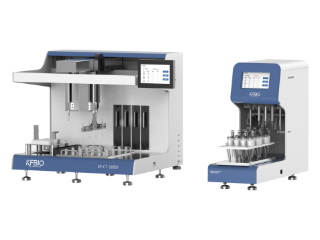

AI-powered Cervical Cancer Screening Solution

AI-powered cervical cancer screening integrated solution includes AI reagents, staining and production equipment, AI-powered initial

diagnosis, and digital slides storage solutions. KFBIO customizes the optimal solutions for customers to meet different needs.

Fully automatic sinking slicing, efficient and clear

Different models of innovative staining

equipment to meet different needs

|  |  | |

|---|---|---|---|

| Model | KF-CT-3000Y | KF-CT-4000Y | KF-CT-024E |

| Main Advantages | Suitable for small and mediummedical institutionsOpen operation space, simpleoperation | Meet most users' requirementsClosed, high staining efficiency Independent stain reagent directinjection system, improve production efficiency | Follcws the principle of traditional sedimentaticnproduction method. One-key automatic operatiolSuiteble for various sccnarios such as laboratoryproduction and ccrvical canccr cell scrccning |

| Sample Quantity | 24 | 48 | 24 |

| Speed | 24 slides/45min | 48 slides/45min | 24 pieces / 55 minutes |

| Production Technology | Reaction chamber natural sedimentation technology | Reaction chamber natural sedimentation technology | Reaction chamber type natural sedimentation technology |

| Production Technology | Single sample injection | Four-sample parallel injection technology | Four-sample parallel injection technology |

| Stain Method | Four channels liquid separation | Independent stain reagent direct injection technology | Independent stain reagent direct injection technology |

| Stain Method | Four channels liquid separation | Independent stain reagent direct injection technology | Independent dye liquid direct injection technology |

| Waste Liquor Disposal | Four channel confluence negative pressure suction | Independent waste liquor extraction and control technique | Independent waste liquid extraction technology |

| Exhaust Gas Filter | - | Closed passive exhaust gas filtration | Closed passive waste liquid filtration |

| Monitor Reagentand Consumables | - | - | |

| Sample Pre-process | - | - | - |

| Process Gynecological andNon-gynecological Samples |